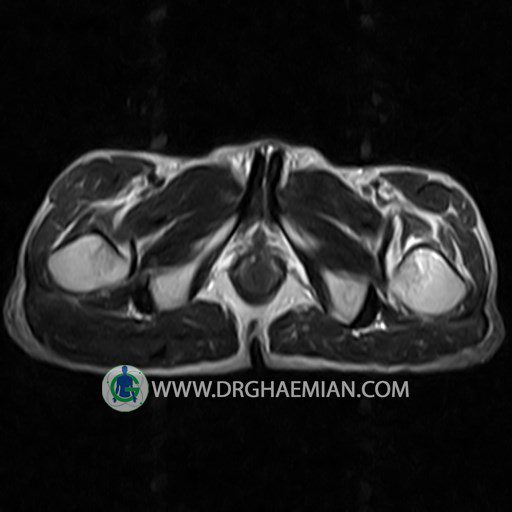

پزشکان اغلب از تصویربرداری ام آر آی برای تشخیص و درمان عارضه های پزشکی که فقط با استفاده از اشعه ایکس یا میدان مغناطیسی و امواج رادیویی قابل مشاهده است، استفاده می کنند. دستگاه ام آر آی تصاویر دقیق از ساختار های داخلی بدن ایجاد می کند. در این کیس استئومیلیت لگن، آتروز و سنیویت دیده می شود.

HIP JOINT MRI

( without contrast )

Technique : coronal STIR , coronal T2 , Axial T1 , axial T2 .

REPORT:

Each femoral shaft has normal margins and contains a normal bone marrow signal .

The imaged muscles and the lesser pelvis show no abnormalities .

– Heterogeneous signal change (high T2/STIR , low T1) in proximal metaepiphysis of left femur without articular surface irregularity suggestive for bone bruise (stress fracture?), osteomyelitis & arthritis and marrow infiltration (less probable)

– Left hip joint effusion suggestive for synovitis

are seen.

COMMENT: Clinical correlation and MRI with contrast are recommended.